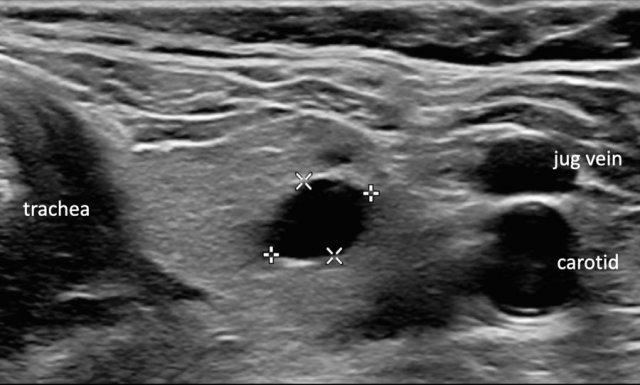

Cyst

Hình ảnh mô tả một nang tuyến giáp điển hình.

Không cần đánh giá thêm.